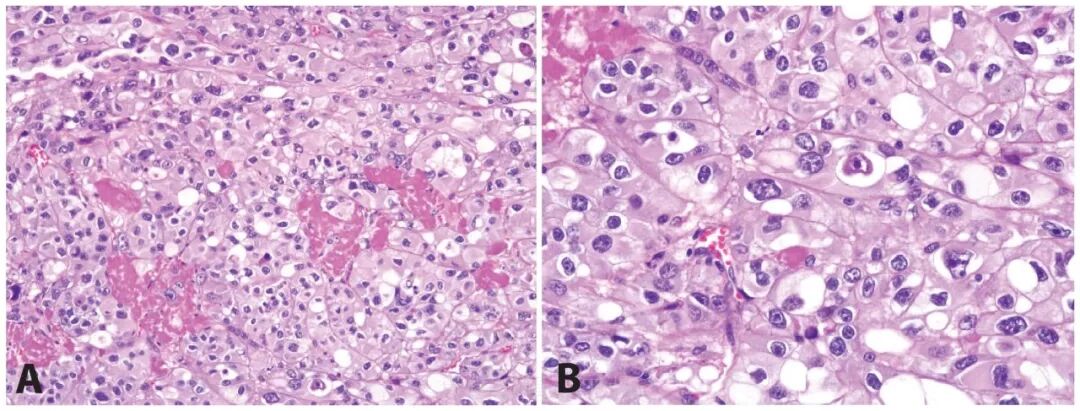

HLRCC综合征相关肾细胞癌最初归为乳头状肾细胞癌,少见情况下归为集合管癌。最初报道的HLRCC家族中4例高级别肾脏肿瘤局灶可见乳头状结构、瘤细胞胞质丰富、细胞核大、伴包涵体样嗜酸性核仁。其中一例为混合性管状乳头状结构,另一例则为实性、囊性、肉瘤样区域混合。后来提出该肿瘤中最显著的形态学特征为细胞核大、伴显著包涵体样核仁。不过,这些特征可能仅存在于个别细胞中。

3. HLRCC综合征相关肾细胞癌常呈乳头状及管状生长;典型情况下,这一肿瘤局灶伴显著包涵体样核仁及染色质边集。

4. HLRCC综合征相关肾细胞癌中,部分病例的细胞核特征并不显著。

最近一项对9例FH胚系突变患者肾肿瘤的分析中,仅1/3具有乳头状结构。这类肿瘤中的纤维脉管轴心常水肿或玻璃样变,常见微乳头状结构。所有肿瘤均为多种结构混合,如管状乳头状、实性、囊性(常伴囊内乳头状或管状乳头状结构)。常见与集合管癌的形态学重叠,且促纤维结缔组织增生的间质中伴浸润性癌及炎症。HLRCC相关肾细胞癌的管状囊性区有时可见显著核仁。